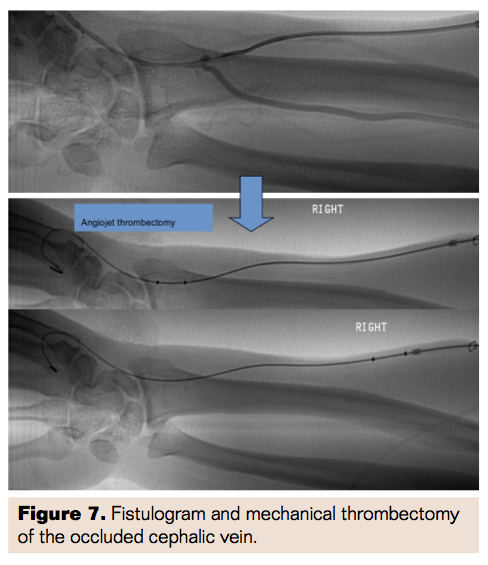

A 72-year-old male with chronic renal insufficiency and stage 4 chronic kidney disease had previously undergone a radiocephalic AVF. Two months prior to presentation, he was noted to have a diminishing thrill over his fistula on follow-up. An elective fistulogram was scheduled for salvage of the access site. On the date of the fistulogram, a bruit was no longer present and the fistula was noted to be occluded. After access of the cephalic vein was obtained, a fistulogram was performed, followed by Angiojet mechanical thrombectomy of the occluded cephalic vein (Figure 7). This was followed by angioplasty with a 6 mm compliant balloon (Figure 8). Further angioplasty was performed on a persistent stenotic segment using a 6 mm noncompliant balloon with resolution of stenosis and complete restoration of flow (Figure 9).